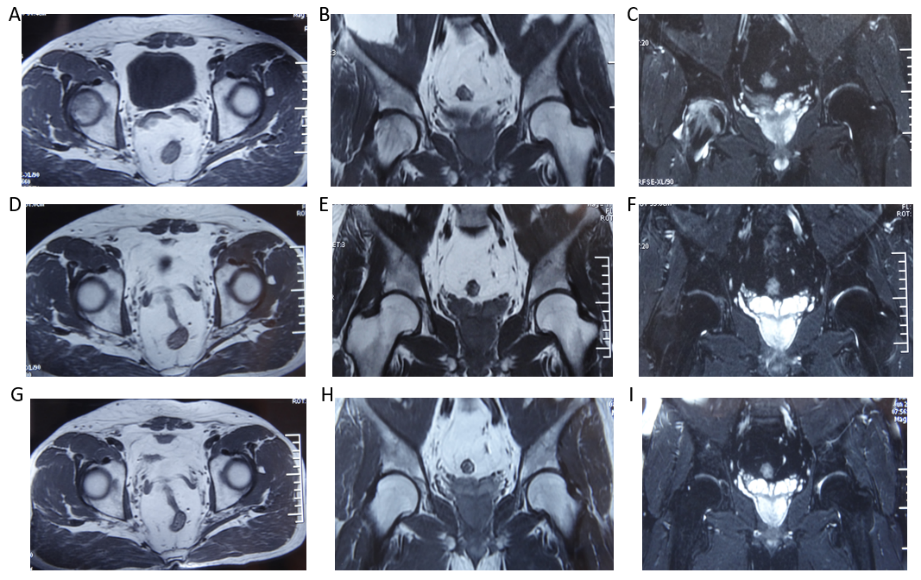

病例,男 54岁,股骨头坏死1期,治疗3个月痊愈

治疗前A-C:MRI右侧股骨头大面积异常信号,骨软骨信号模糊消失。治疗3个月D-F:,异常信号消失,患者恢复正常工作。愈后2年随访 G-I:MRI信号正常。

A 54 year old male with stage 1 femoral head necrosis recovered after 3 months of treatment. Prior to treatment, there was a large area of abnormal signal in the right femoral head on A-C: MRI, and the bone cartilage signal was blurred and disappeared. After 3 months of treatment for D-F, abnormal signals disappeared and the patient resumed normal work. Follow up for 2 years after recovery: G-I: MRI signal is normal.